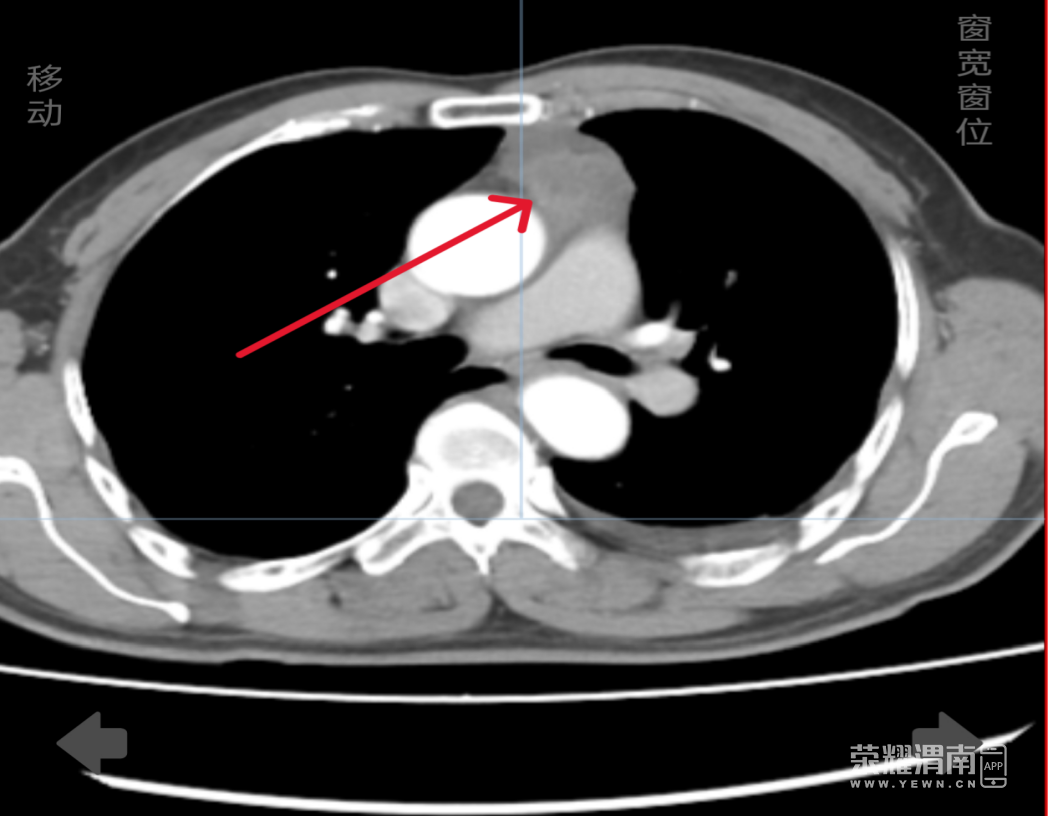

9月9日,渭南市中心医院胸外科团队成功完成一例剑突下胸腔镜中转正中开胸手术,为一名72岁胸腺瘤患者解除病痛。该手术展现了医院在复杂胸外科疾病诊疗方面的综合实力。

患者因间歇性胸背部疼痛入院,经检查发现胸腺瘤位置特殊,与周围组织关系复杂。胸外科负责人李卫国团队经充分评估,决定先行尝试胸腔镜微创手术。术中发现肿瘤与重要血管紧密粘连,分离难度大、出血风险高。李卫国与王宏涛教授根据术前预案,果断决定转为正中开胸手术,在充分沟通获得家属同意后,顺利完成肿瘤切除。患者术后恢复良好,已康复出院。